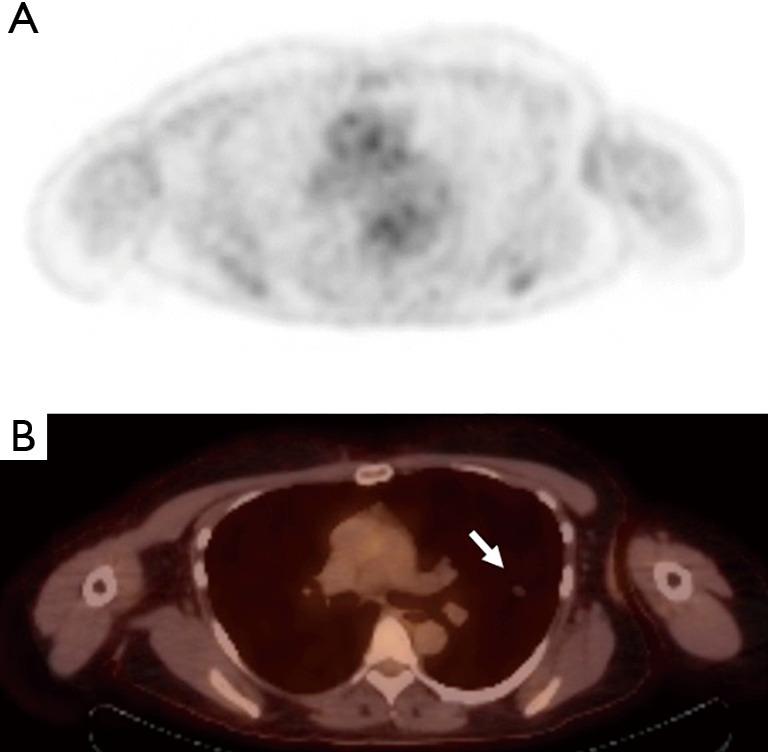

Alveolar adenoma of the lung: multidisciplinary case discussion and review of the literature.

J Thorac Dis. 2020 Nov;12(11):6847-6853. doi: 10.21037/jtd-20-1831.

18F-FDG PET/CT rarely provides additional information other than primary tumor detection in patients with pulmonary carcinoid tumors.18F-FDG PET/CT 除了能检测原发性肿瘤外,很少能为肺类癌肿瘤患者提供其他额外信息。

Alveolar adenoma of the lung: unusual diagnosis of a lesion positive on PET scan. A case report.肺腺泡腺瘤:PET扫描显示阳性病变的罕见诊断。病例报告。